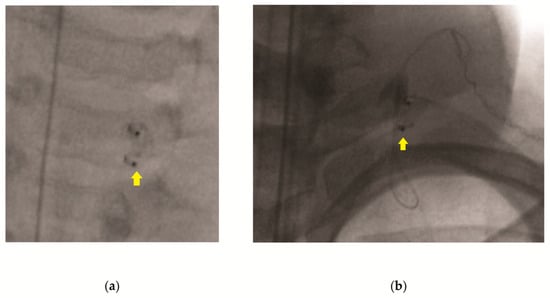

All operations were performed by the senior author (J.E.B.). The surgical technique involves first opening the chest wall incision, followed by the removal of the VNS generator. Next, adhesions are removed from the lead wire in order to ensure the free movement of the wire. Gentle pressure is applied to the anterior neck at the level of the helical coils while traction is applied inferiorly to the lead wire at the chest wall incision (Video S1). Once the lead wire is removed, the neck is evaluated using intraoperative fluoroscopy, looking for residual wire (Figure 1). If the lead wire is completely removed, the chest incision is closed and the patient is extubated and transported to the recovery room. If fluoroscopy reveals that retained lead wire is present (Figure 1b), the neck incision is explored, and the residual lead wire removed. Lead wire removal is confirmed by intra-operative fluoroscopy. Both incisions are then closed, and the patient is extubated and transported to the recovery room.

Figure 1. Radiographs showing coils and lead wire following attempted single-incision removal. (a) A-P radiograph showing residual coils but no wire; (b) lateral radiograph showing coils with residual guide wire. Yellow arrows indicate helical coils.